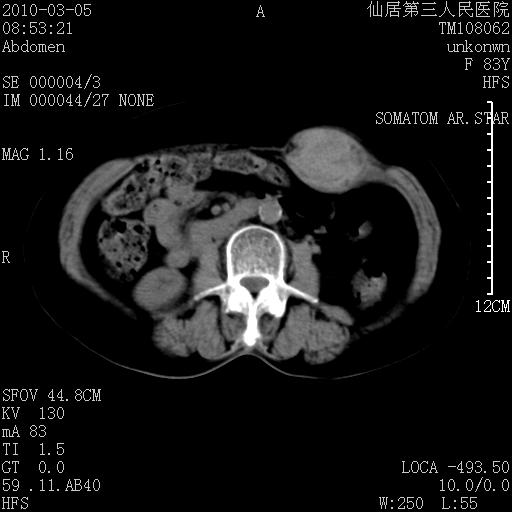

标题: CT24879:腹直肌病变。在线等。

女性,83y,腹痛一周。

增强看看,mfh可能性大,次之可考虑血肿、bfh、转移瘤、神经纤维瘤、侵袭性韧带样纤维瘤等。肝内钙化灶,右肾结石。